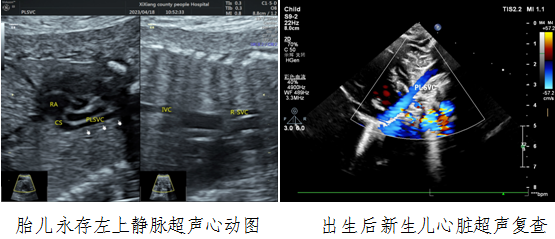

病例一,30岁,孕22w+,G2P1,既往产检未见胎儿心脏结构异常。2023年4月到西乡县21点策略

例行常规产前超声检查,21点技巧中心

对口帮扶贾玄慧医生,超声发现胎儿存在先天大血管发育异常——永存左上腔静脉,指导孕妇进行产前咨询及产后随访。胎儿出生后1天,贾玄慧医生立即对该新生儿进行了心脏复查,结果确诊永存左上腔静脉诊断明确。